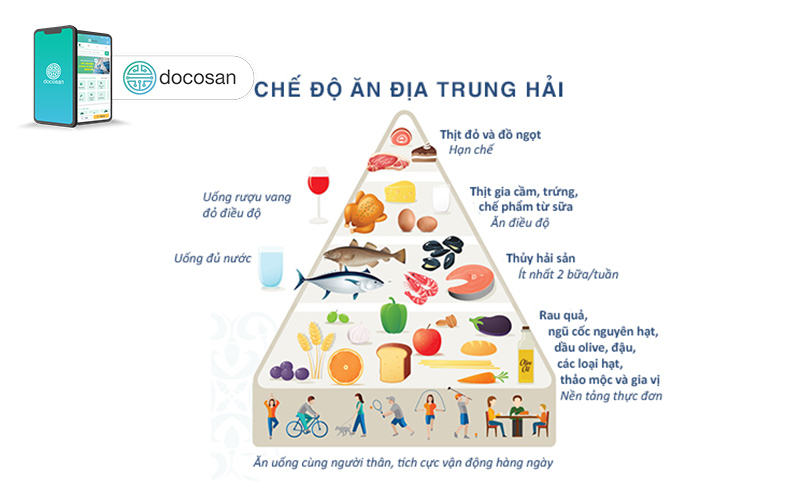

Đầu tiên, người bị gan nhiễm mỡ độ 1 cần biết chế độ ăn Địa Trung Hải. Mặc dù chế độ ăn này không chỉ được tạo ra cho những người bị bệnh gan nhiễm mỡ độ 1, nhưng lối ăn uống này kết hợp các loại thực phẩm giúp giảm tối đa chất béo trong gan của bạn: chất béo lành mạnh, chất chống oxy hóa và carbohydrate phức tạp. Chế độ ăn Địa Trung Hải có thể bao gồm các loại thực phẩm như sau:

- Cá và hải sản

- Trái cây tươi

- Các loại ngũ cốc

- Các loại hạt

- Dầu ô liu

- Rau

- Quả bơ

- Các loại đậu